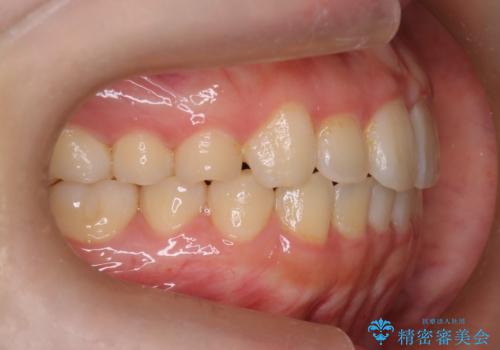

【インビザライン】前歯の凸凹をなおしたい

- 前歯のガタガタを主訴に来院されました。

インビザラインで綺麗な歯並びになり、患者さんには大変満足していただきました。

インビザラインは軽度叢生治療において優れた選択肢となります。